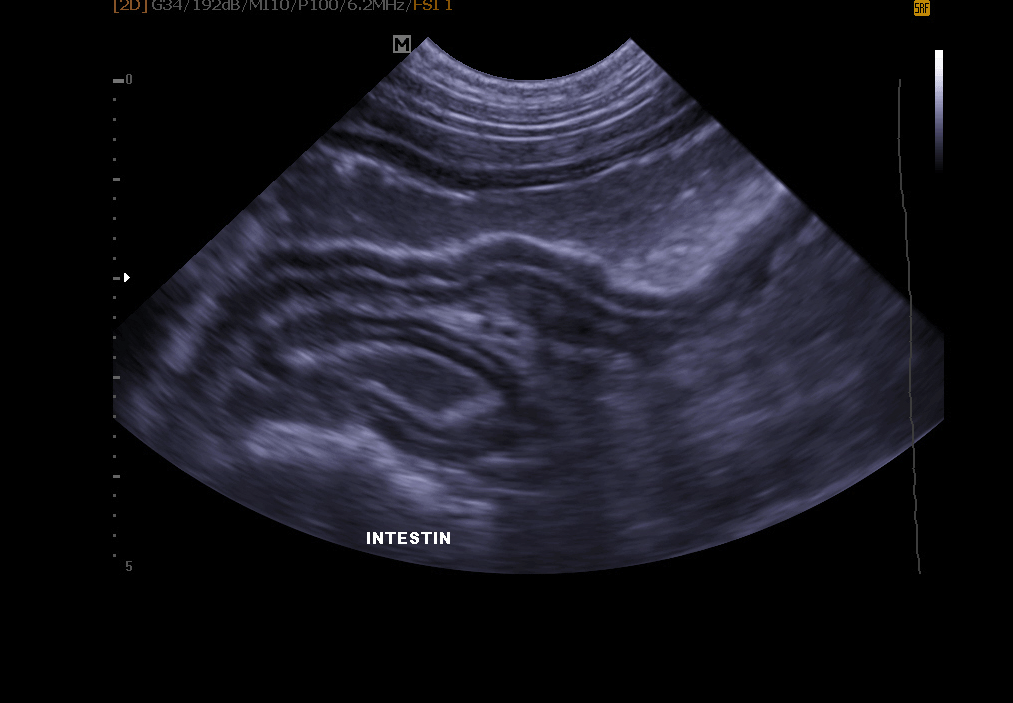

Abdominal ultrasound:

Abdominal ultrasound: it allows exploration of the bladder (search for stones, polyps, tumor), kidneys, spleen, liver, pancreas and other abdominal organs.